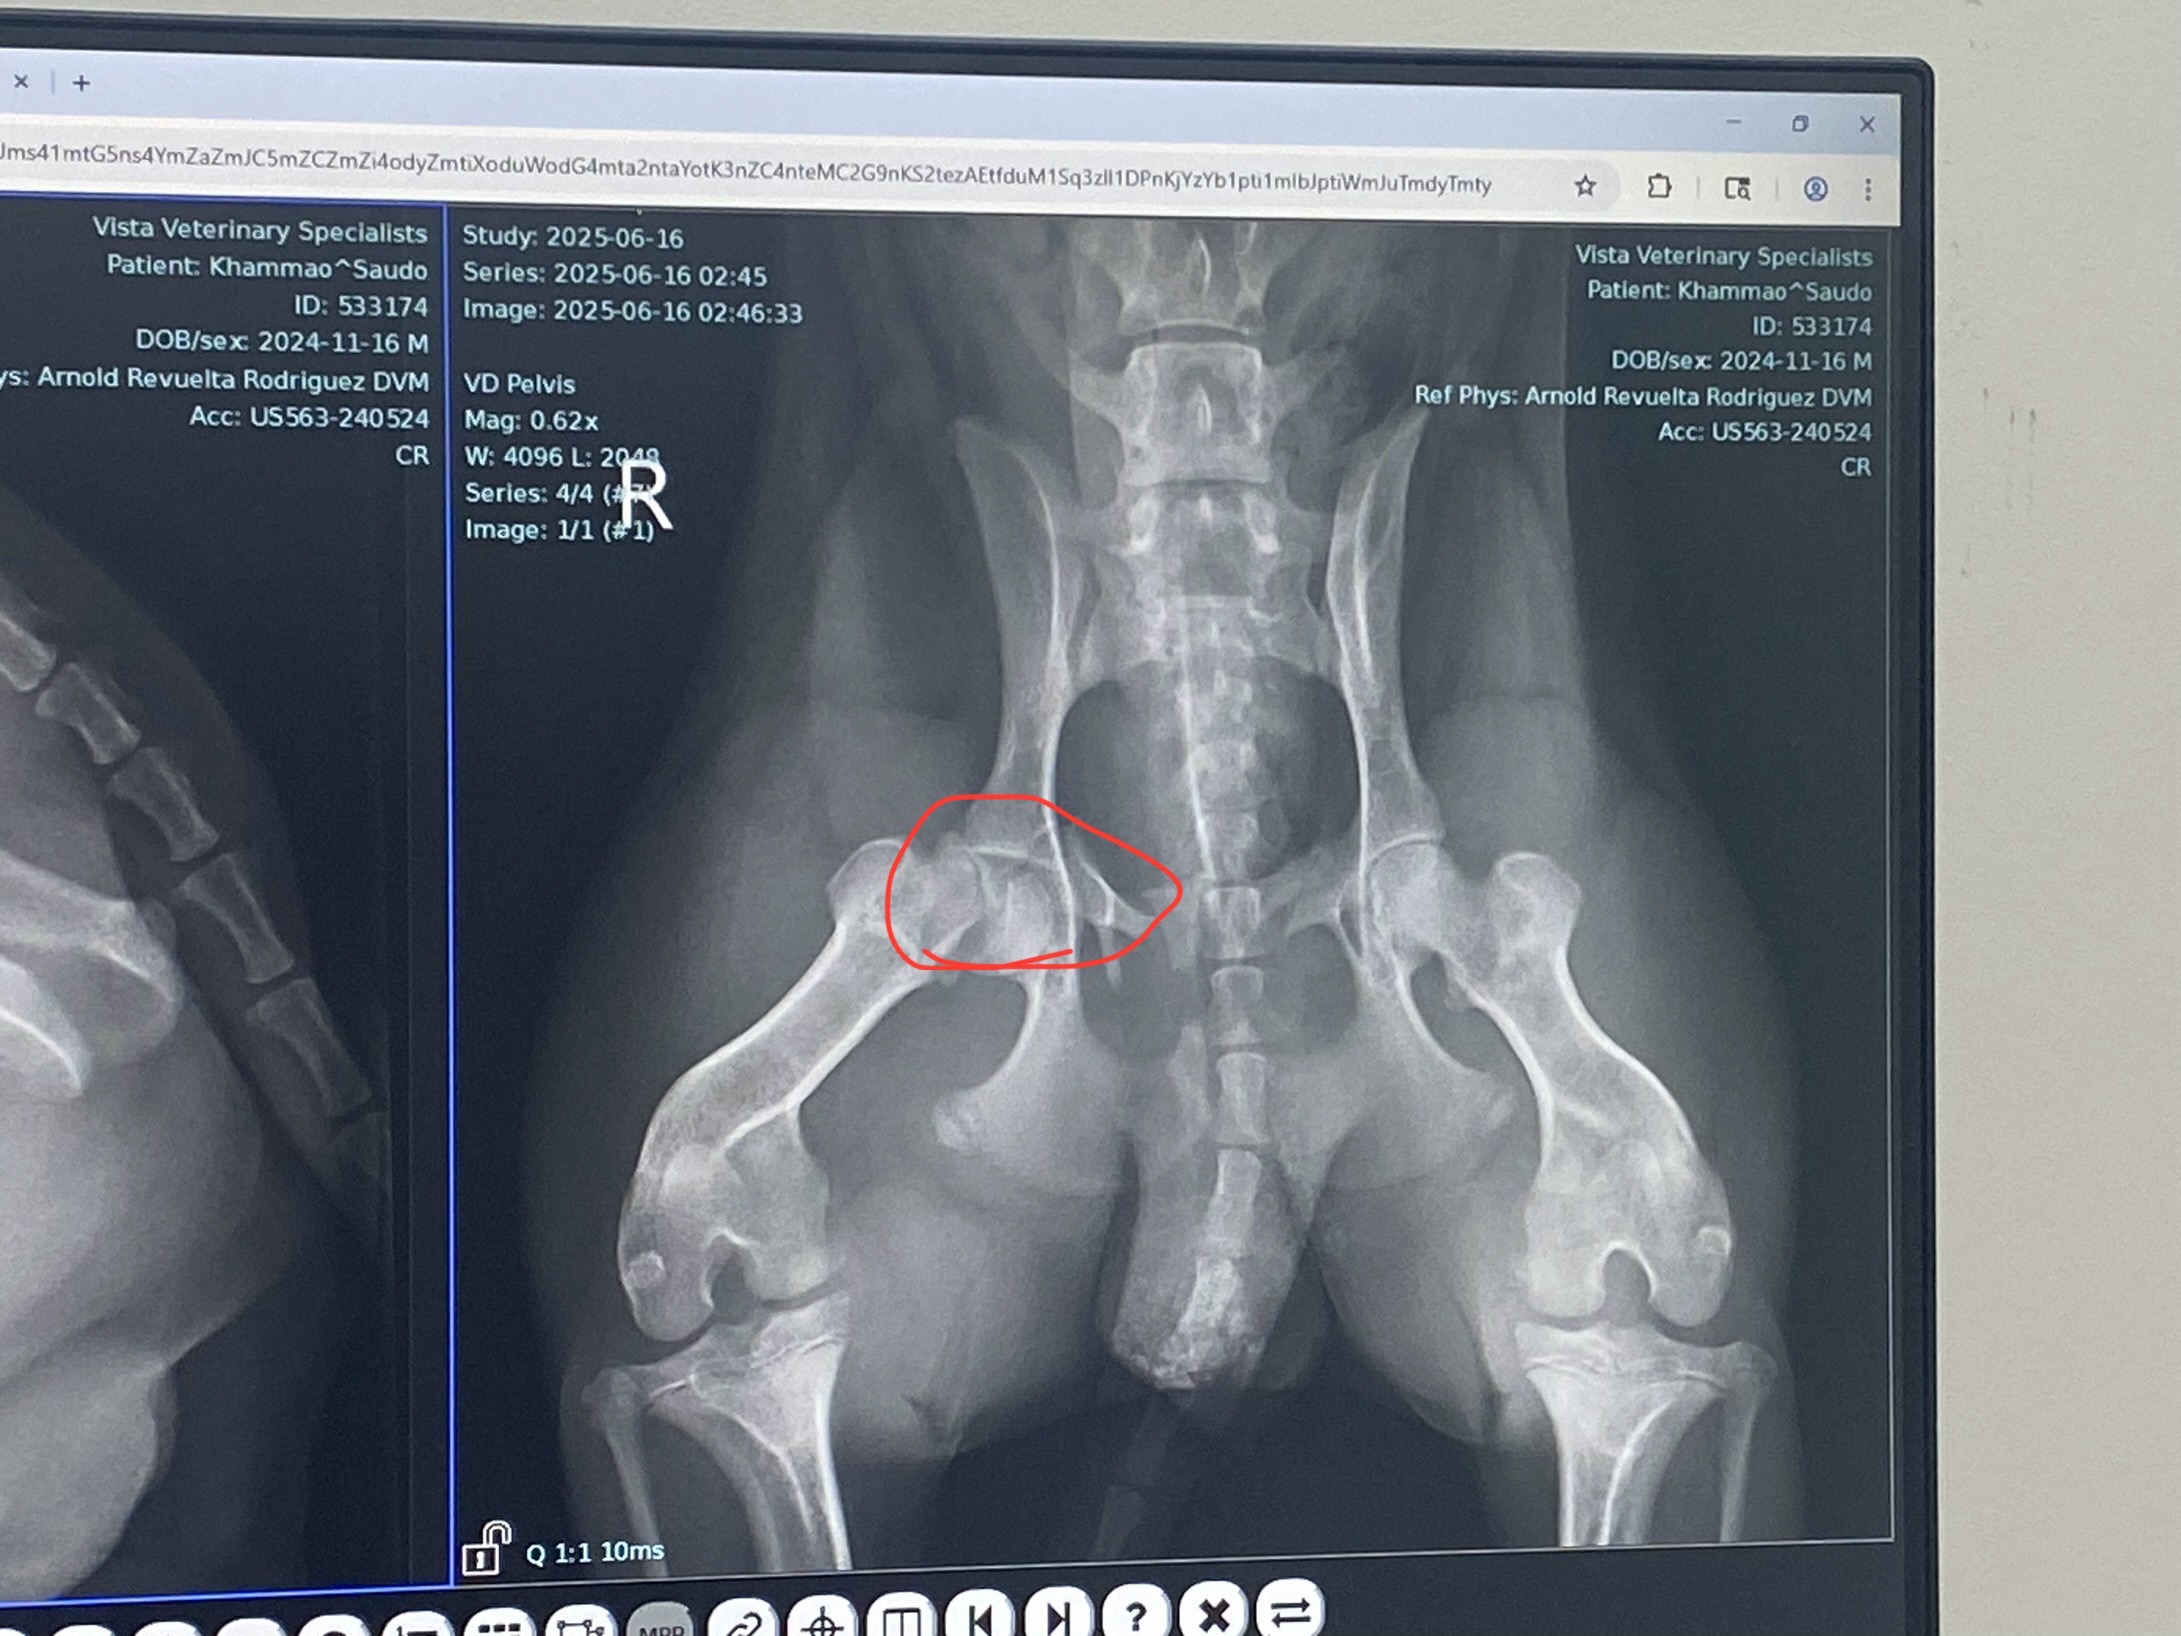

On June 16th, our beloved pup Saudo was hit by a car. He’s currently in stable condition, resting at home and being kept as comfortable as possible with painkillers and steroids. That night, he got loose from his harness and ran across the street—where the accident happened. We rushed him home and then straight to the hospital. The injuries he sustained will have long-term effects.

The surgery he needs won’t be a permanent fix, but it will allow his wound to heal properly and reduce his pain. Without this surgery, Saudo will have to live in daily pain. If I can’t afford it, I may be faced with the heartbreaking decision to euthanize him—and that’s something I can't imagine, not just for me, but for his sister too. They're inseparable, and even that one day apart at the hospital left her heartbroken. She knew something was wrong.